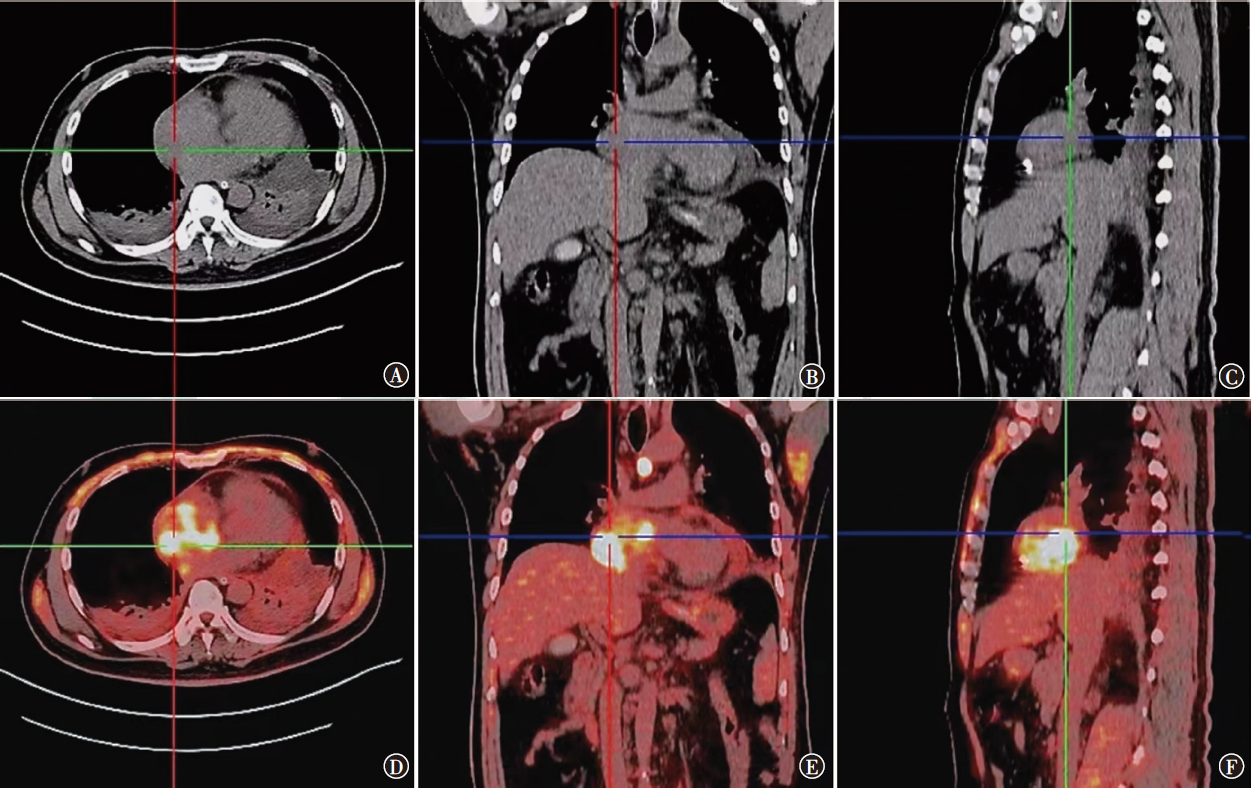

原发性心脏血管肉瘤是一种来源于血管内皮的恶性肿瘤,极为罕见且预后极差,病理诊断特异性及敏感性较高的标志物是CD31和CD34,手术不能根治性切除,姑息放疗、系统化疗和抗血管生成靶向治疗可延长患者生存期。现报道1例心脏原发血管肉瘤患者的诊疗经过,并就相关文献进行复习,以提高对该类疾病的认识。